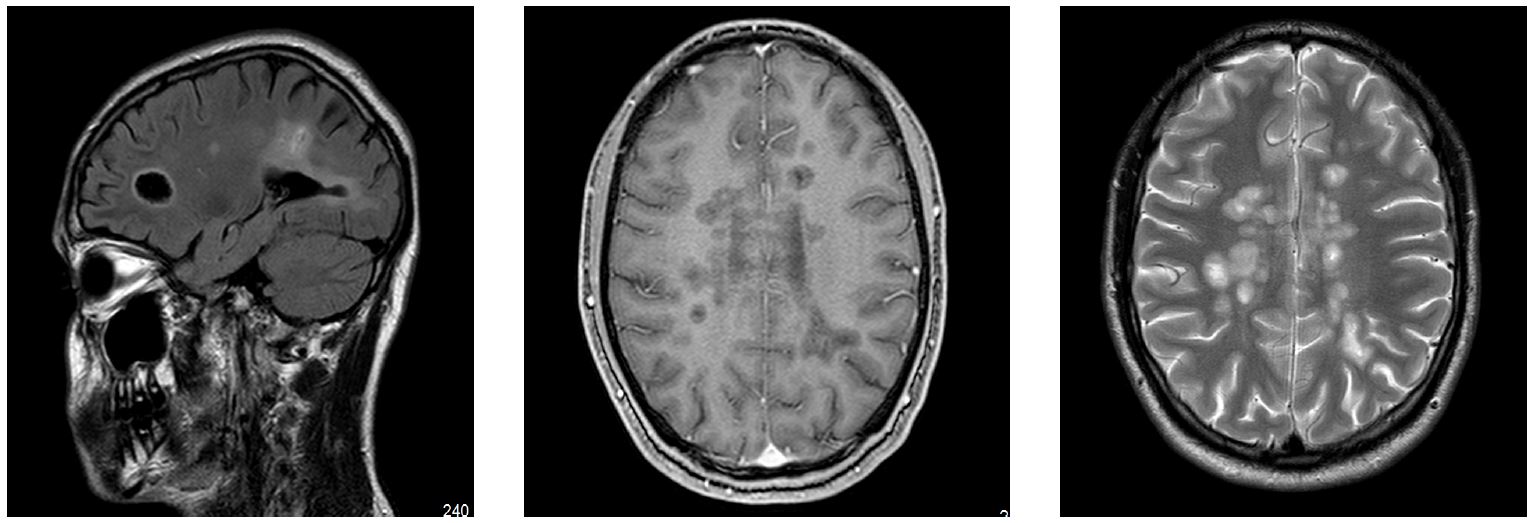

Рис. 3. МРТ-изображения в режимах T2 ВИ и FLAIR, 06.11.2020

МРТ-исследования на фоне терапии ПИТРС натализумаб (рис. 3): 06.11.2020: положительная динамика, очаги 3–21 мм, с уменьшением размеров, один очаг копит контраст в левой теменной доле.

На МРТ от 09.09.2021: нарастание атрофических изменений мозолистого тела, полиморфизм очаговых изменений, тенденция к уменьшению очагов, без признаков активности процесса.